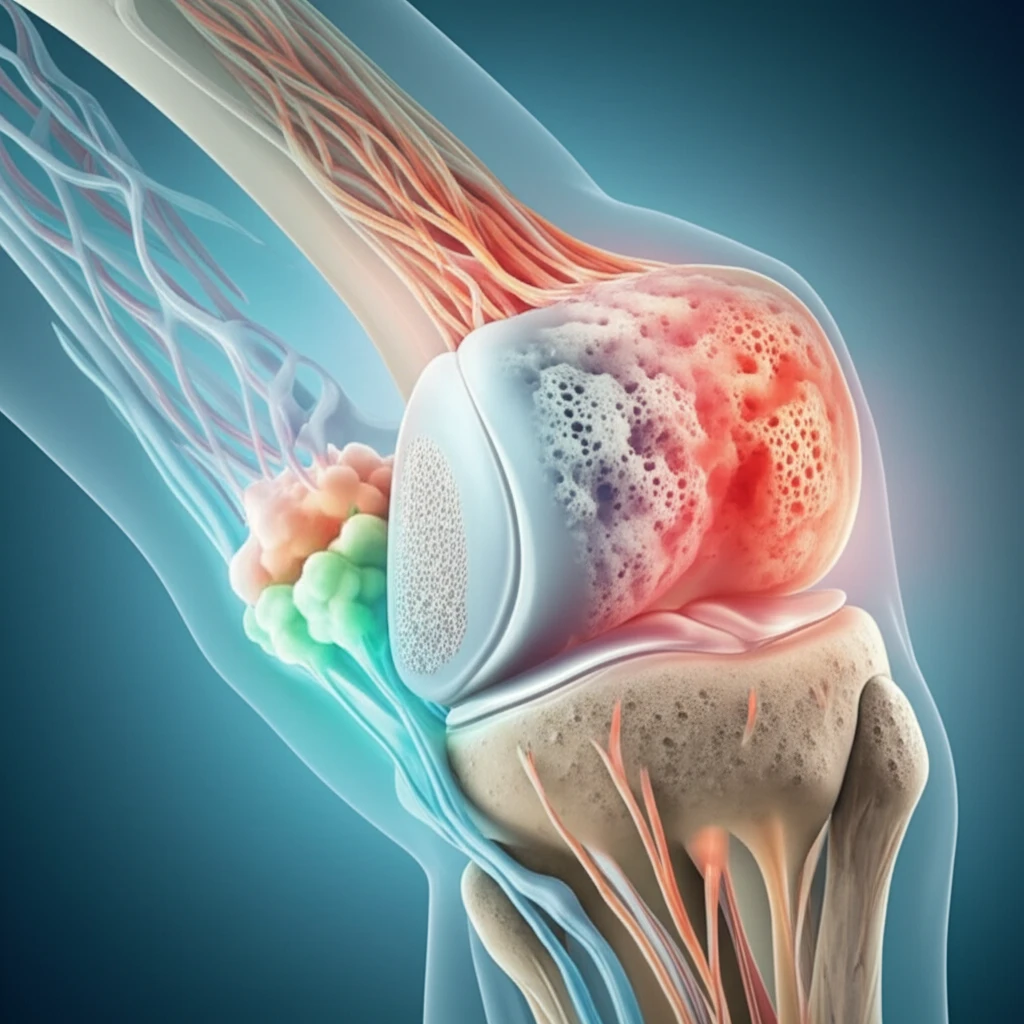

For those struggling with joint pain and cartilage injuries, a promising area of research has emerged: using bone marrow aspirate concentrate (BMAC) to stimulate healing from within. BMAC is a concentrated sample taken from your own bone marrow, rich in cells and growth factors that can aid in the repair and regeneration of damaged cartilage.

The appeal of BMAC lies in its potential to offer a cost-effective and less invasive alternative to traditional surgical interventions. Instead of relying on external materials or complex procedures, BMAC harnesses the body's natural healing capabilities to address cartilage defects.

Bone marrow aspirate concentrate is more than just a collection of cells; it's a complex cocktail of elements that work together to promote healing:

- Mesenchymal Stem Cells (MSCs): These are like the body's construction crew, capable of transforming into various types of tissues, including cartilage.

- Growth Factors: These are the signaling molecules that tell cells what to do. In BMAC, they encourage cell growth, reduce inflammation, and promote tissue repair. Key growth factors include: